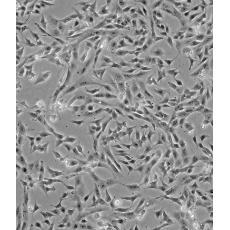

產(chǎn)品名稱 SK-N-SH [SKNSH]

中文名稱 人神經(jīng)母細胞瘤細胞

組織來源 神經(jīng)母細胞瘤;骨髓來源;女性

生長特性 adherent

形態(tài)特征 epithelial

細胞描述 SK-N-SH細胞系由J.L.Bieder建系,它與SK-N-MC所不同的是倍增時間較長且多巴胺-β-羥基酶水平較高。 SK-N-SH在細胞介導的細胞毒性試驗中用作靶細胞系。